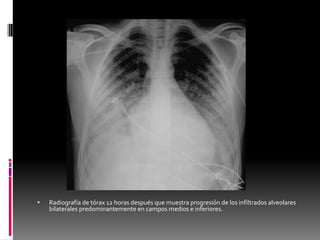

 El dato radiológico más común

consiste en un patrón alveolar

segmentario, que corresponde a la

hemorragia alveolar dispersa.

 En general, las anomalías

radiológicas afectan a las zonas

periféricas de los lóbulos inferiores

de los campos pulmonares.

Radiografía de tórax 12 horas después que muestra

progresión de los infiltrados alveolares bilaterales

predominantemente en campos medios e

inferiores.